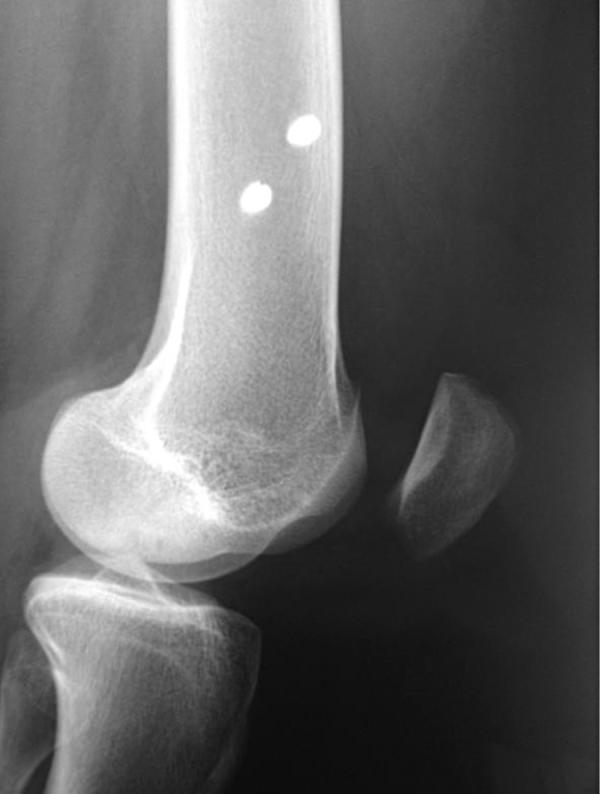

The medial patellofemoral ligament (MPFL) injury has been considered instrumental in lateral patellar instability after patellar dislocation. Consequently, the focus on the study of this ligament reconstruction has increased in recent years. The MPFL femoral anatomical origin point has great importance at the moment of reconstruction surgery, because a graft fixation in a non anatomical position may result in medial overload, medial subluxation of the patella or excessive tensioning of the graft with subsequent failure. In the pediatric population, the location of this point is highlighted by the presence of femoral physis. The literature is still controversial regarding the best placement of the graft. We describe two cases of skeletally immature patients in whom LPFM reconstruction was performed. The femoral fixation was through anchors that were placed above the physis. With the growth and development of the patients, the femoral origin point of the graft moved proximally, resulting in failure in these two cases.

髌股内侧韧带(MPFL)损伤被认为是髌骨脱位后髌骨外侧不稳定的重要因素。因此,近年来对该韧带重建的研究关注度有所增加。MPFL在股骨上的解剖学起点在重建手术中非常重要,因为将移植物固定在非解剖位置可能会导致内侧负荷过重、髌骨内侧半脱位或移植物过度张紧继而失效。在儿童群体中,由于存在股骨骨骺,这一点的位置更为突出。关于移植物的最佳放置位置,文献中仍存在争议。我们描述了两例骨骼未成熟患者进行LPFM重建的病例。股骨固定是通过置于骨骺上方的锚钉进行的。随着患者的生长发育,移植物的股骨起点向近端移动,导致这两例手术失败。